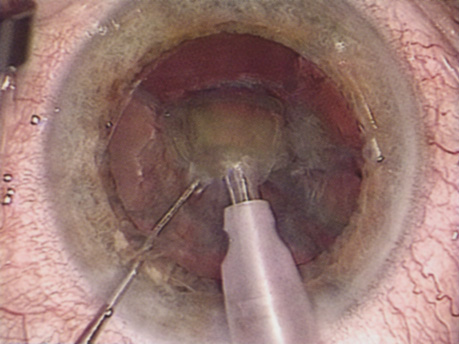

Hydrodissection can be performed after the surgeon has successfully completed capsulorrhexis.97 If the capsulorrhexis is not intact, fluid forced around the interior of the capsule may cause the bag to splay open. With capsulorrhexis, hydrodissection is a safe and extremely useful maneuver. Hydrodissection can be thought of as two maneuvers: hydrodelineation and cortical cleaving hydrodissection. By placing a 27-gauge cannula on a syringe filled with balanced saline solution (BSS), the surgeon can direct fluid beneath the residual anterior capsular rim to create a cleavage plane. Depending on the direction the fluid wave takes, different lamellae of the cataract will be separated. Hydrodelineation is the term used when the cleavage plane separates the adult nucleus from the fetal nucleus or the adult nucleus from the more peripheral epinucleus. Hydrodelineation often results in the characteristic golden ring sign (Fig. 11). Cortical cleavage occurs when the cortex is separated from the capsular bag (Fig. 12). Finding the cortical cleavage plane may be facilitated by gently lifting the capsular margin away from the cortex with the BSS cannula before injecting. Several small bursts of fluid allow the surgeon to monitor progress of the fluid wave. When dealing with a soft nucleus, the authors strive to perform true cortical cleaving hydrodissection. For a hard nucleus, hydrodelineation allows manipulation of less of the nuclear bulk, although the remaining epinuclear shell must be addressed in an additional step. Hydrodelineation is particularly useful if the nucleus is not freely mobile after cortical cleaving hydrodissection.

Fig. 11. A crisp “golden ring” is seen from the fluid cleft between the epinucleus and nucleus with hydrodelineation.